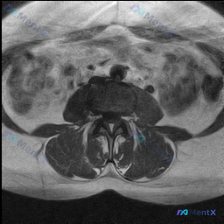

刚整理了一份腰椎MRI读片病例,只有单张轴位T2加权图像,把完整的分析思路整理出来和大家分享。 一、影像基本信息 这是一张腰椎MRI轴位T2加权图像,清晰度良好,解剖结构辨识度高: - 扫描水平为腰椎单个节段(大概率L4/5或L5/S1,具体需结合矢状位确认) - T2序列特征符合典型表现:脑脊液高...

整理了一份腰椎MRI读片讨论,给大家分享一下思路。 病例影像基础信息 本次仅提供放射影像-腰椎MRI-T2序列-轴位单张图像,扫描层面为腰椎某一节段,视觉判断符合腰4/5或腰5/骶1椎间盘水平,无临床病史、体征及其他检查资料,核心问题是明确该层面是否存在椎间盘病变相关影像学表现。 影像具体读片结果...

看到这张腰椎MRI-T2轴位影像,大家第一反应是什么?问题问的是椎间盘病变,整理一下分析思路和大家分享。 一、影像基本信息 这是腰椎椎间盘层面(最可能为L4/5或L5/S1)的T2轴位扫描,我们先梳理所有客观发现: 1. 椎间盘情况:中央区域信号较正常稍低,提示椎间盘脱水变性;但后缘形态完整,没有明...